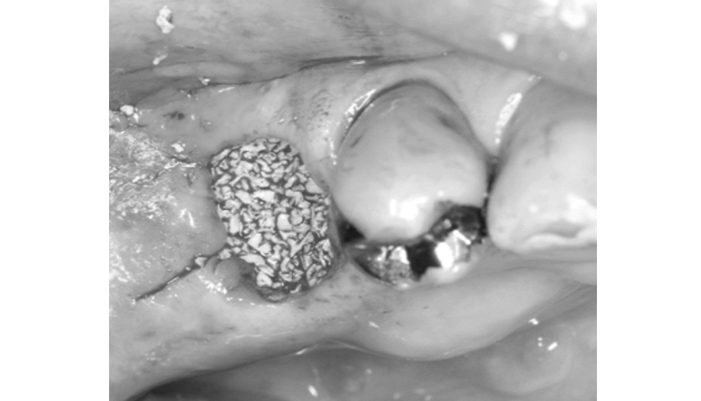

治療前

患者様は「インプラントをするために骨をできるだけ残したい」とのご希望で来院されました。診査の結果、歯根破折により保存は難しく、抜歯が必要な状態でした。また、抜歯後は骨が吸収しやすいリスクが高い状況でした。そのため、抜歯と同時に骨補填材を填入し、メンブレンで保護することで、歯槽堤の形態維持を図り、将来のインプラントに備えた治療を行いました。

| 主訴 | 抜歯後のインプラント希望。 |

|---|---|

| 治療期間 | 1回 |

| 治療費 | ¥55,000(税込) |

| 治療内容 | 抜歯後の骨の吸収を防ぐため骨補填材を用いた処置を行いました。 |

| 治療のリスク | 感染や腫れが生じる可能性があります。 |